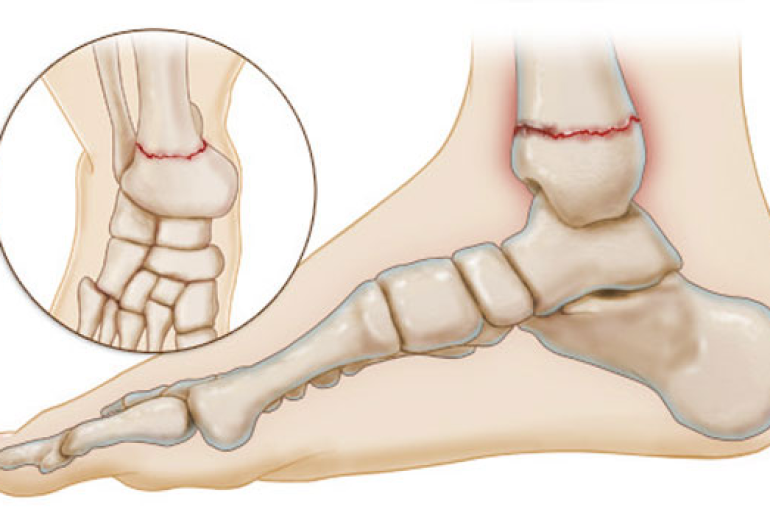

شکستگی مچ پا به معنی ترک خوردگی یا شکستگی یکی از استخوانهای مچ پا است. مچ پا از سه استخوان اصلی تشکیل شده است: استخوان تیبیا (درشتنی)، استخوان فیبولا (نازکنی)، و استخوان تالوس. شکستگی مچ پا ممکن است در هر یک از این استخوانها رخ دهد و شدت آسیب میتواند از یک ترک کوچک تا شکستگی کامل و جا به جایی استخوانها متفاوت باشد.

- تصویربرداری رادیوگرافی (اشعه ایکس): این روش معمولترین راه تشخیص شکستگی استخوانها است. اشعه ایکس به پزشک امکان مشاهده دقیق استخوانهای مچ پا و تشخیص نوع و محل شکستگی را میدهد.